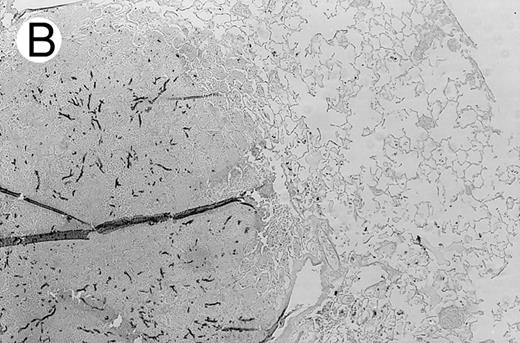

Three groups of X-CGD mice were studied: (1) control X-CGD mice; (2) X-CGD mice challenged 10 to 14 weeks after transplantation with MSCV-91Neo–transduced X-CGD BM; and (3) X-CGD mice challenged 5 to 8 weeks after transplantation with mixtures of wild-type and X-CGD BM cells. The results are summarized in Table 2. There were no deaths during the 17 to 21 days after challenge except for one mouse in the second group who died of complications of anesthesia on day 1. All 16 control X-CGD mice that were not transplanted developed lung disease after respiratory exposure to A fumigatus conidia. A common finding in lung tissue was the presence of multiple foci of granulomatous microabscesses that also contained occasional giant cells (Fig 3A). Rare hyphae were also seen. Larger inflammatory nodules containing numerous neutrophils and hyphae were seen in some mice (Fig 3B). Large abscesses with necrotic centers or regional bronchopneumonia were also occasionally observed (not shown). In 4 of 4 X-CGD mice transplanted with marrow transduced with the low-titer MSCV-h91Neo vector, who had only 1% to 2% NBT+ PB neutrophils at time of challenge, lung disease similar to that seen in untransplanted X-CGD mice was seen (Table 2). However, only minimal, if any, inflammatory changes were seen in 9 of 9 X-CGD mice with ≈50% to 80% NBT+ circulating neutrophils after transplantation with BM transduced with the high-titer vector (Table 2). Lungs appeared either normal (except for macrophages containing colloidal carbon that was administered along with conidia to mark the site of delivery) or contained occasional collections of mononuclear cells, typically in perivascular or peribronchial locations (Fig 3C). These findings were similar to those seen in lungs of wild-type mice after challenge with these numbers of A fumigatus conidia (unpublished observations, 1996).

Pulmonary findings 17 to 21 days after intratracheal instillation of A fumigatus conidia in X-CGD mice. Lung tissue was obtained 17 to 21 days after intratracheal challenge with 150 to 500 A fumigatus conidia, and stained with hematoxylin and eosin (A and C) or Grocott methamine silver (B). Representative photomicrographs obtained from three different mice are shown (original magnification × 100). (A) Untransplanted X-CGD mouse. Granulomatous microabscesses are seen, with occasional giant cells. (B) Untransplanted X-CGD mouse. Large inflammatory nodules with a central collection of neutrophils and numerous hyphae are seen. (C) X-CGD mouse transplanted with marrow transduced with the high-titer MSCV-m91Neo retrovirus. Occasional mononuclear cells in perivascular spaces and alveoli are seen, along with macrophages containing colloidal carbon (arrows) that was administered with the conidia to mark the site of delivery.